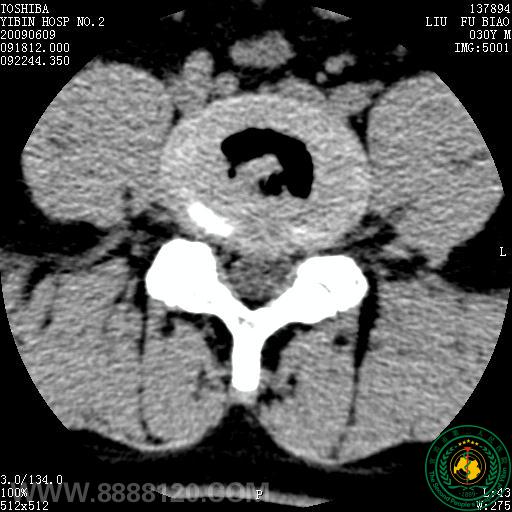

患者为30岁青年男性,经我院CT扫描诊断为腰4/5正中后型椎间盘突出症。经我科李登科、林川两位主治医师术前严格筛查及讨论,认为该患者适合进行臭氧髓核消融,无该手术禁忌症,遂于69日晨830分在经严格消毒后的介入手术室完成了该例手术。术中及术后患者未诉不适。术后于我院CT室复查,见腰4/5椎间盘髓核区臭氧存留。

术前CT                                                                      椎间盘穿刺(1